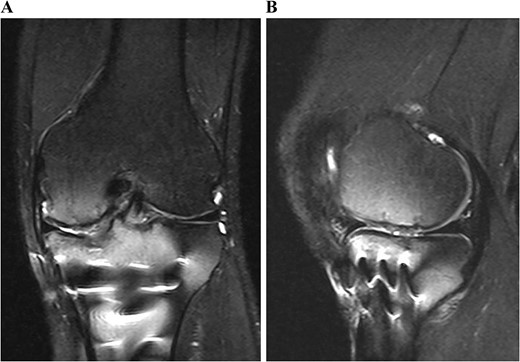

Postoperative T2-weighted fat-suppressed magnetic resonance images at 1 year after surgery. The transplanted cultured cartilage was successfully integrated without any delamination.

Postoperative MRI at 1 year after the surgery showed that the transplanted cultured cartilage had successfully integrated without any delamination (Fig. 6). A second-look arthroscopy was performed to evaluate the condition of the transplanted cartilage while removing the plate. The cartilage defect of the medial femoral condyle was covered by hyaline cartilage-like tissue. The depressed articular surface of the medial tibia plateau was smooth without stepping off (Fig. 7). One year after the surgery, the patient resumed daily life and sports activities without any complaint. The patient’s range of motion of the knee was full, and Lysholm’s knee score was 95.